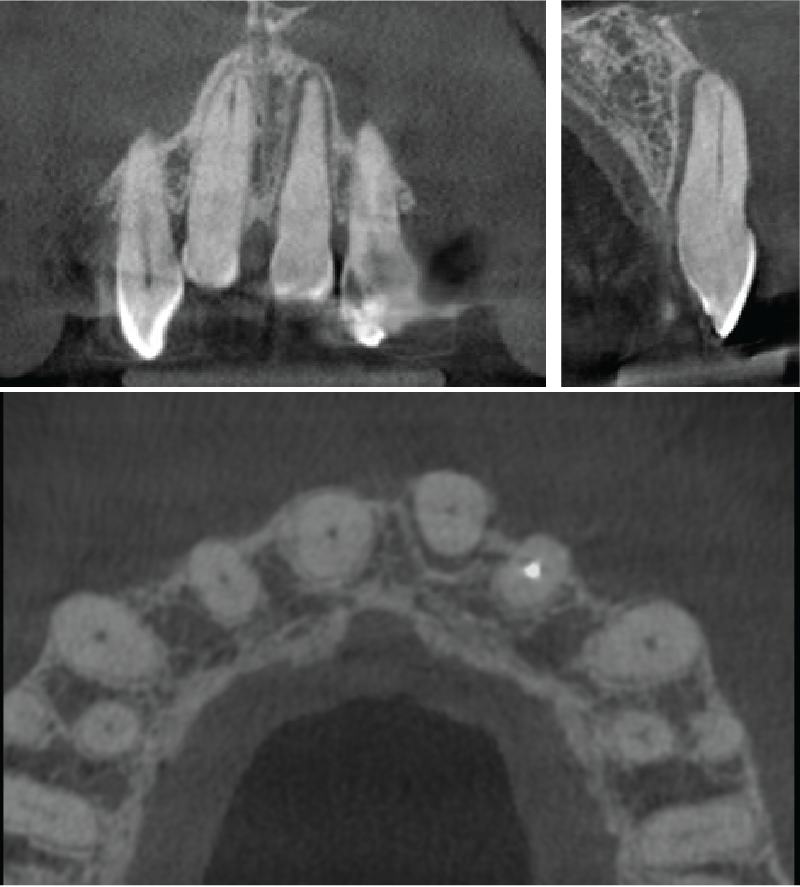

The UL1 is displaced buccally with no root fracture. The apical vessels are likely torn due to the displacement. No alveolar fracture is seen, although there is a little buccal cortical plate still attached to the root of UL1.

Coronal, sagittal and axial slices through the UL1

Volume rendered image showing the UL1

Learning from this case:

Small volume CBCT can be used additionally to 2D X-rays in the diagnosis and management of dentoalveolar trauma after a fall, accident or other mechanism of injury. CBCT is able to show luxation, root fractures and alveolar fractures.